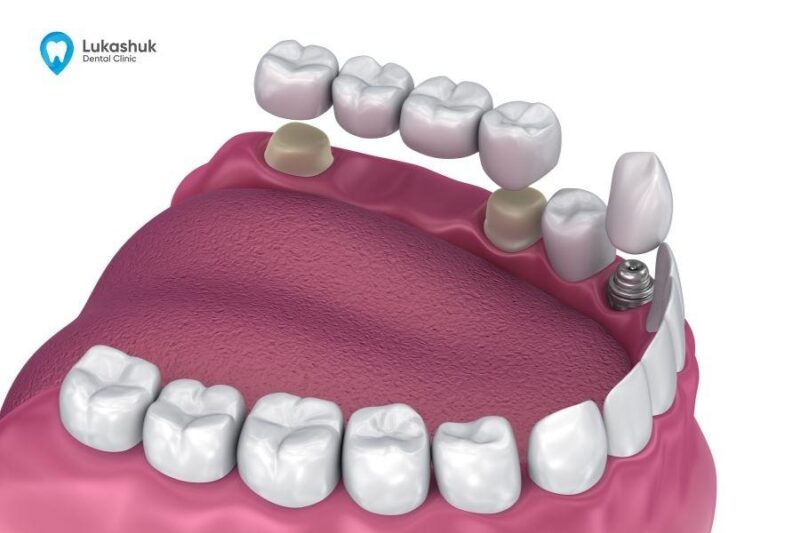

Полная конструкция, позволяющая восстановить зуб в ходе операции имплантации называется системой имплантов. Она включает: винт (имплантат), абатмент, формирователь десны, коронку. Производители стоматологических материалов предлагают комплекты изделий, которые позволяют выполнить восстановление зуба комплексно. Все их элементы полностью совместимы друг с другом, что обеспечивает высокий результат процедуры.

Популярные корневидные импланты зубов (винтовые и цилиндрические) имитируют форму корня.

Винтовые имеют резьбу, с помощью которой вкручиваются в кость. Цилиндрические выполнены без резьбы, но имеют пористую поверхность, которая способствует приживлению имплантата.